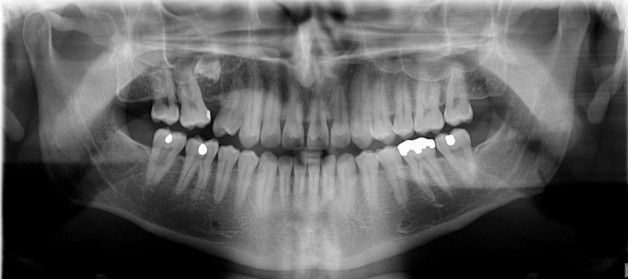

Panoramik röntgen, çenelerin, tüm dişlerin, çene ve dişlerdeki bir çok rahatsızlığın tek bir filmde

görülmesini sağlayan röntgen filmleridir.

Panoramik röntgen, çene ve dişlerde gözle görülemeyen çürük, kist ve tümör gibi oluşumların teşhisinde

gereklidir.

Panoramik röntgen bir çok diş çürüğü, çenelerdeki kistik ve tümoral oluşumlarla ilgili erken teşhis olanağı

sağlar.

Tüm dişlerin görüntüsü tek bir röntgen üzerinde görülebilir.

Panoramik röntgen tüm dişlerin ve çene kemiğinin daha az ışın alarak birlikte görüntülendiği bir

tomografik röntgen çeşididir.

Dijital sitemin kullanılması görüntü kalitesini artırmakta ve kişinin aldığı radyasyon miktarını belirgin

şekilde azaltmaktadır.